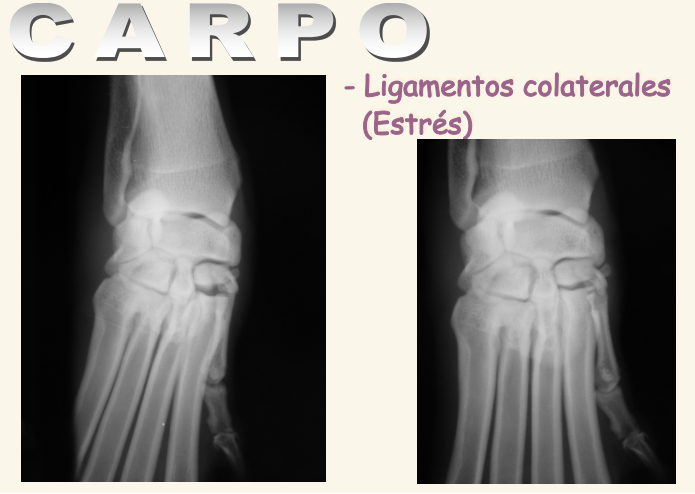

Carpo

Problemas mas comunes:

- Hiperextensión o hiperflexión (Estrés)

- Luxación o subluxación

- Fracturas

- Malformaciones

IMPORTANTE, CAE EN EXAMEN: En carpo y taso hay que hacer proyecciones de estres (empujar los dedos para ver como se comporta bajo estrés) para valorar los los ligamentos colaterales